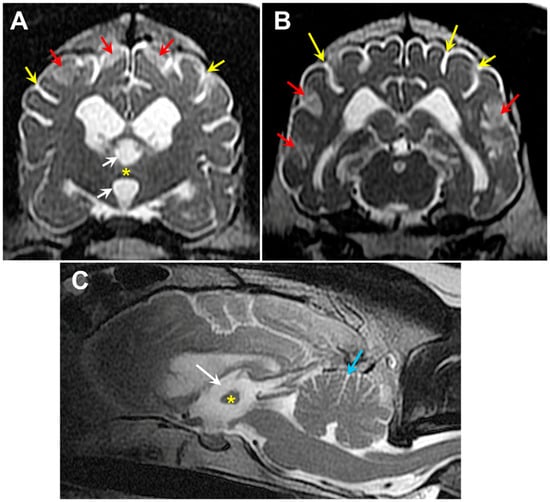

3.1. Microscopic Findings